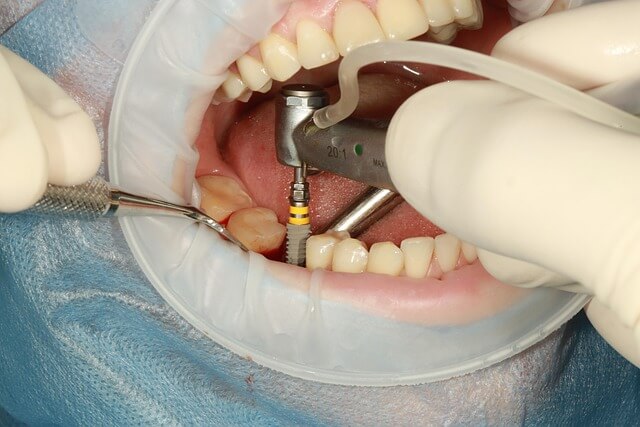

2. 잇몸치료 방법: 전문가가 권하는 단계별 접근

* 흔히 잇몸치료라고 하면 한 번의 진료로 끝날 거라 생각하지만 실제로는 단계별로 나누어 접근하는 경우가 많습니다. * 처음에는 간단한 세정으로 시작하고, 상태가 심하면 잇몸 깊은 곳까지 관리하는 정밀 치료가 필요하죠. * 제가 상담해봤을 때도 잇몸치료는 개인 상태에 따라 달라져서 획일적인 방식은 거의 없었습니다. * 결국 맞춤형으로 접근했을 때 결과가 훨씬 안정적이었습니다. * 이런 고민 하셨다면, 전문가의 조언을 듣고 내 상황에 맞는 단계별 방법을 선택하는 게 가장 현명한 길입니다.

- 기본 관리 단계

- 잇몸 깊숙한 치료 단계

- 정기 검사와 관리 단계